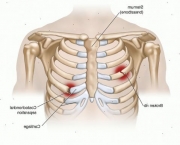

Existem casos em que a dor causada pela doença vem acompanhada de uma vermelhidão ou mesmo de um inchaço nas regiões mais dolorosas. Quando isso acontece se chama Síndrome de Tietze.

O diagnóstico da Costocondrite pode ser feito pelo médico através de pressão realizada sobre a área em que acontece o encontro das costelas e do osso do peito. Quando existe algum tipo de inflamação nessa região a causa mais comum é a Costocondrite. Em geral o médico realiza mais um teste para ter certeza de que não se trata de um problema cardíaco e outras doenças que também poderiam causar dores no peito.